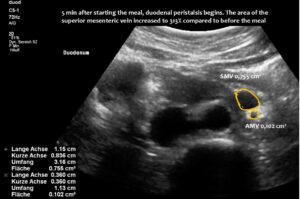

Normal size of the superior mesenteric vein which is slightly slimmer than the superior mesenteric artery as long as the patient was fasting. However, due to the limited space in the flat upper abdomen the superior mesenteric artery already is shifted to the left side of the aorta instead of lying precisely in front of it.

Here, the unique mechanism causing compression of the duodenum by the enlarged superior mesenteric vein is demonstrated. In contrast to conventional SMA syndrome, the superior mesenteric vein acts as a pillar against which the aorta presses, thus obstructing the duodenum. It is important to be aware of the variability in the position of the superior mesenteric artery in patients with a flat abdominal cavity. When the stomach is full, it may shift further to the left (or right) of the SMA than in the fasting position.

Enlargement of the superior mesenteric vein can be observed as early as five minutes after eating, progressing to fivefold enlargement of the transsectional area after seven minutes.